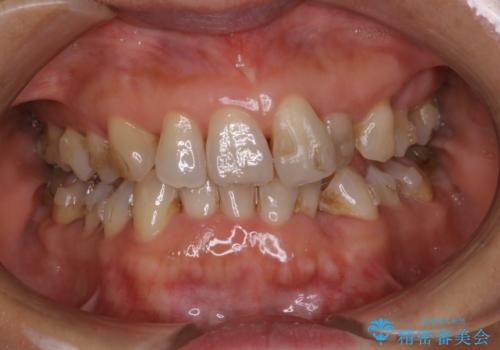

インビザラインの治療中の患者様のクリーニング前後写真です。

- インビザラインの矯正治療中に歯石や着色(ステイン)が付着してしまっていたため、歯科衛生士による専門的クリーニングを行いました。

今回はお口全体に歯石や着色(ステイン)が付着していたため、自費のPMTC(クリーニング)60分コースをご案内し、徹底的に除去しました。